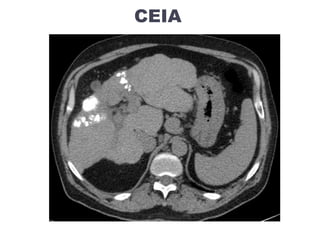

CEIA

Technique de radiologie interventionnelle locorégionale

Injection par voie artérielle +/- sélective :

Doxorubicine / cisplatine